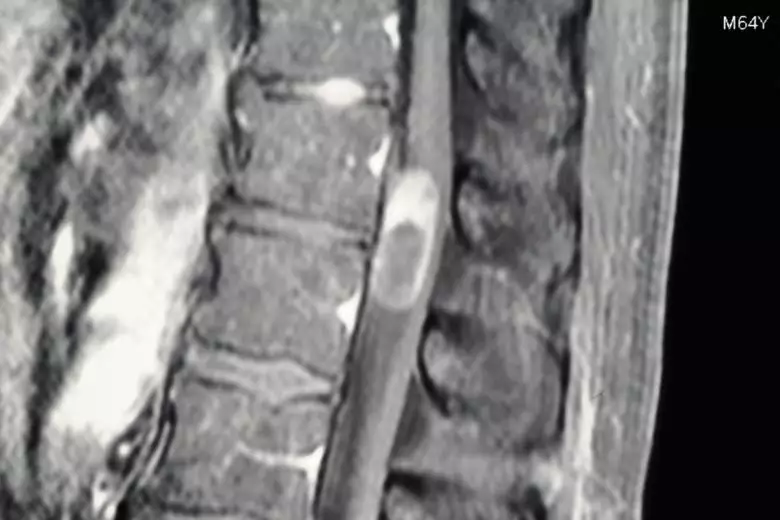

Bildgebende Verfahren sind aus der modernen Medizin nicht mehr wegzudenken, auch bei der Behandlung von Wirbelsäulentumoren. Sie ermöglicht es Ärzten, einen detaillierten Einblick in die Struktur und Funktion der Wirbelsäule zu erhalten, ohne dass invasive Eingriffe nötig werden. Mittels verschiedener Bildgebungsverfahren können Tumore in der Wirbelsäule lokalisiert, ihre Größe bestimmt, das Wachstumsmuster verstanden und mögliche Auswirkungen auf umliegende Gewebe und Strukturen beurteilt werden. All dies sind entscheidende Informationen für die Sicherung der Diagnose, die Behandlungsplanung, aber auch die Nachsorge nach einer Therapie.